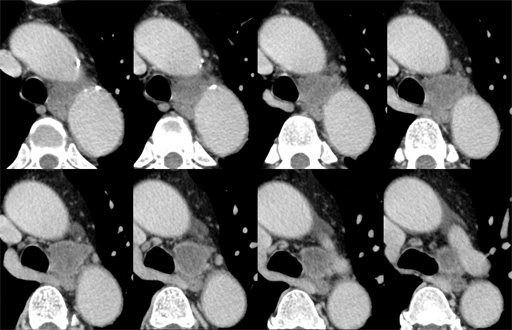

症例7 : 図4 胸部CT 縦隔条件(thinsection)